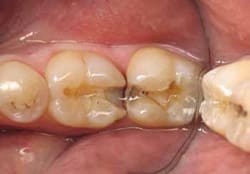

Therefore, a high wear-resistant composite (Venus Diamond) in shade A2 was placed as the final composite increment, and the occlusal morphology was developed using a set of composite instruments developed by the author (RU Composite Instruments Kit, CK Dental, https://www.ckdental.net). After the morphology was fully developed, a complete cure was performed (Figure 4).

The final morphology and occlusal adjustment were achieved using a bullet-shaped 7406 carbide bur (Dentsply, https://www.denstply.com). Proper occlusal adjustment is a must, as most postoperative problems with this restoration can be traced to occlusal problems.12 A one-step easy polish can be accomplished using a diamond impregnated brush (Occlubrush, Kerr, https://www.kerrdental.com). The patient received follow-up phone calls at 1 day and 1 week postoperatively to evaluate sensitivity and satisfaction. No sensitivity was reported.